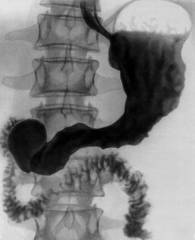

·   Часто случается, что пищевод настолько сужен из-за находящейся в нем опухоли, что эзофагоскоп не проходит. В таком случае для диагноза используется рентгенологическое исследование (Приложение 2), при котором пациент должен выпить особую смесь бария, и затем выясняют места препятствий и размер опухоли.

2.      Используется рентгенологическое исследование желудка со смесью бария (Приложение 2);

·        В некоторых случаях можно исследовать кишку при помощи ирригоскопии (Приложение 2).